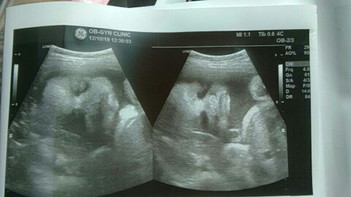

น้อง 32 week แร้ว เห็นหน้าน้องแร้วตื่นเต้นมาก ?